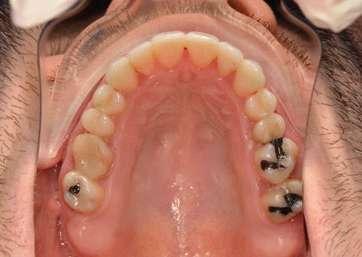

2. Análisis intraoral (Ilustración 2 y 3):

 Clase III molar y canina de Angle bilateral.

 Mordida abierta anterior > 3 mm.

 Compresión maxilar junto con mordida cruzada posterior bilateral.

 Línea media inferior desviada 2 mm hacia la derecha.

Ilustración 2. Fotografías intraorales iniciales de estudio.